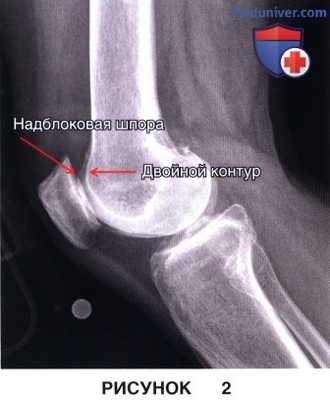

е) Рентгенограммы в боковой проекции должны быть высокого качества и обеспечивать возможность диагностики дисплазии блока (описанные DeJour симптом пересечения, надблоковая шпора и двойной контур) (рис. 2)